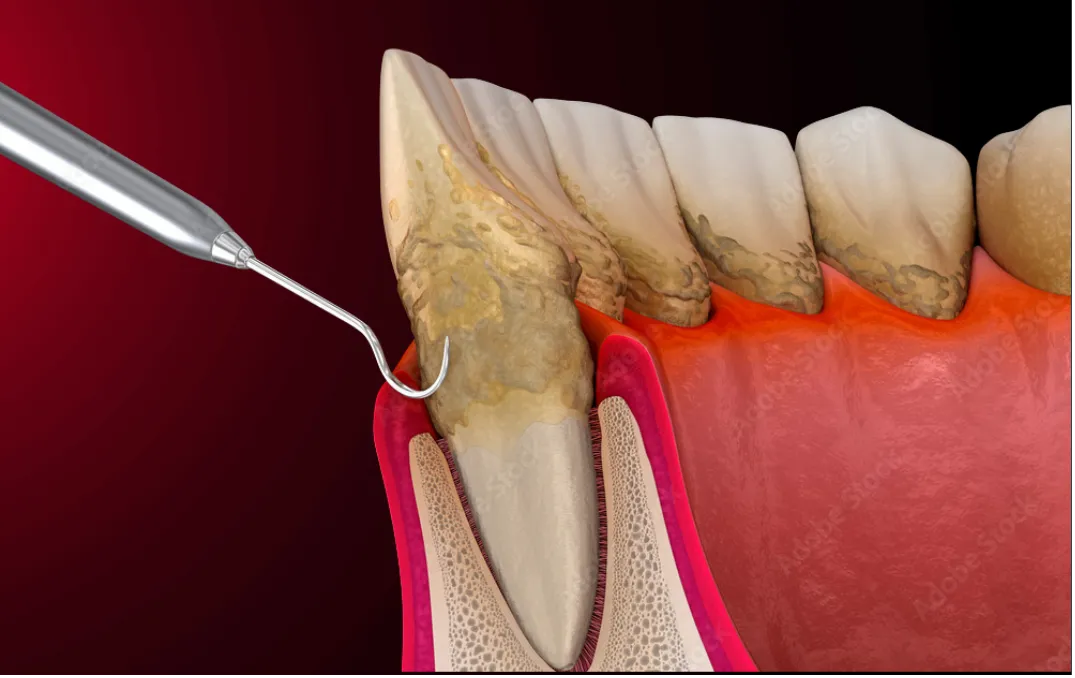

従来の歯科医療は、早期発見と症状のある部分を外科的に修復したり、補綴することを目的としていました。しかし、当院はできだけ欠損しないように、欠損を遅らせるように、予防的な部分に注力し患者さまをマネジメントしていき生涯健康な口腔内で生活出来るようにしています。